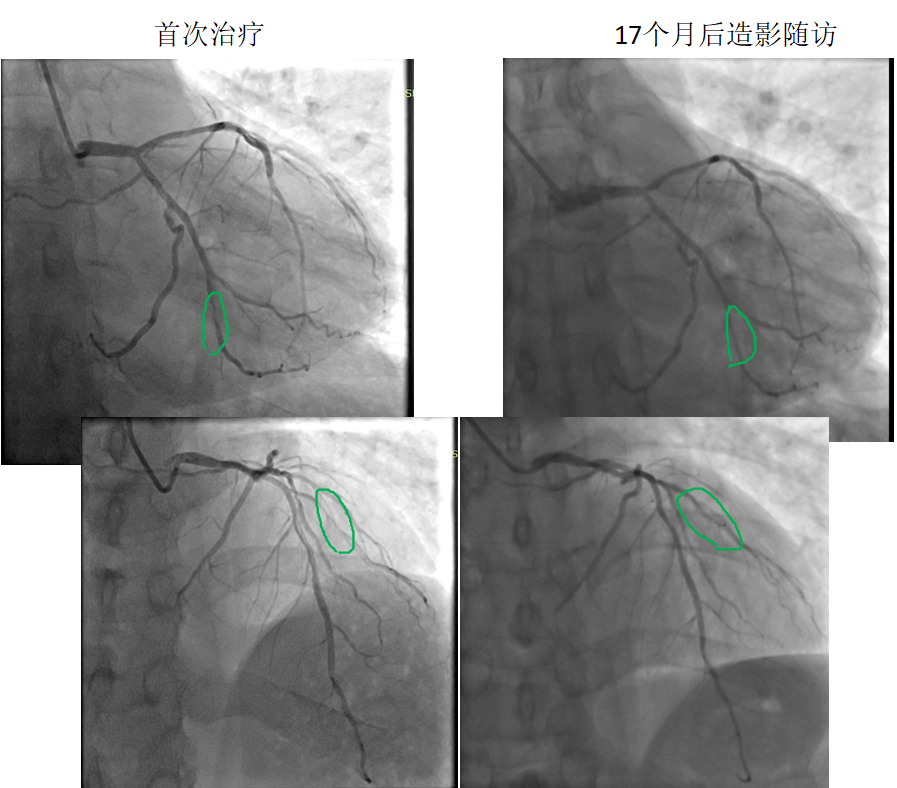

患者:男,38歲

病變部位: OM中遠(yuǎn)段95% ;D1近段90%

使用藥物球囊:2.0 x 20mm; 2.0 x 20mm17個月后造影隨訪:OM中遠(yuǎn)段20% ;D1近段20%